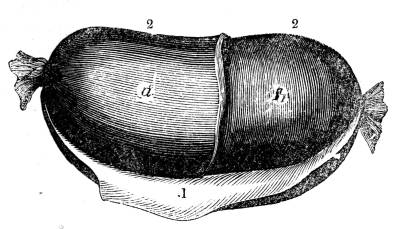

Fig. CXXXIV.—

View of the Respiratory Apparatus in

Man.

1. The Trachea. 2. The right lung. 3. The left lung.

4. Fissures, dividing each lung into, 5. Large portions

termed lobes. 6. Smaller divisions termed lobules. 7.

Pericardium. 8. Heart. 9. Aorta. 10. Diaphragm separating

the cavity of the thorax from that of the abdomen.

357. In man there are two pulmonary bags (fig.

CXXXIV. 2, 3), of nearly equal size, which, together

with the heart, completely fill the large cavity

of the thorax (fig. CXXXIV.), their external surface

being everywhere in immediate contact with

the thoracic walls. One of these bags is placed on

the right side of the body, constituting the right

lung (fig. CXXXIV. 2), and the other on the left,

constituting the left lung (fig. CXXXIV. 3). Each

lung is divided by deep fissures, into large portions

called lobes (figs. CXXXIV. 4, and CXXXV.

6), of which there are three belonging to the

right, and two to the left lung. Each lobe is

subdivided into innumerable smaller parts termed

lobules (figs. CXXXIV. 6, and CXXXV. 6), while the

lobules successively diminish in size until they

terminate in minute vesicles that constitute the

great bulk of the organ (fig. CXXXV. 8).